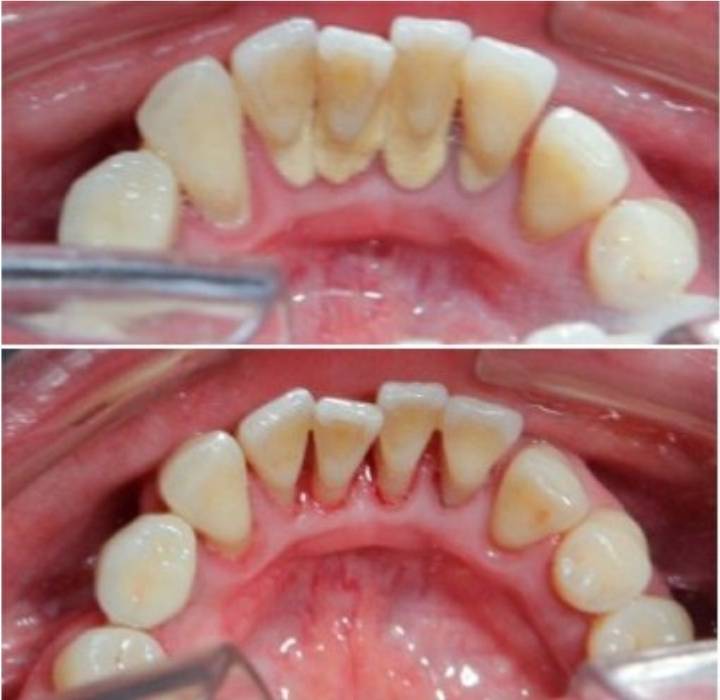

치석이 치아 밑동에 쌓이면

점점 잇몸 내려감

그럼 이렇게 블랙 트라이앵글이 생김

아 물론 저게 보기 싫다고 치석으로 꽉꽉 채워서

보색효과를 내고 다닐 수도 있음

문제는 치석이 쌓이면 더 내려앉아서 뿌리 다 보임..